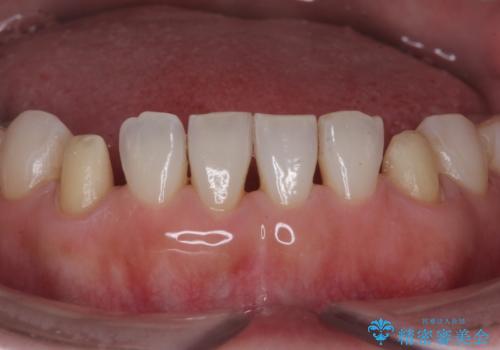

最近右下の犬歯の根の先付近の歯茎に何かできており、違和感があるとのでした。

CTでみたところ、下の犬歯が内側に倒れこんでおり、根の先が顎の骨から出かかっている状態でした。おそらくその影響で犬歯の神経が失活してしまったのであろうと思われます。(フェネストレーションといいます)

検査した結果下の両側の犬歯の神経が失活しており、根の治療が必要な状態でした。